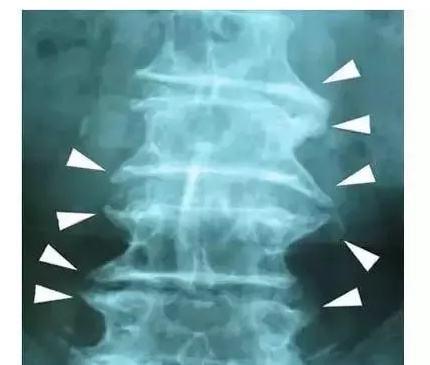

郑州强直医院哪家好?强直性脊柱炎可以通过哪些方法治疗呢

近年来,虽然我们的生活水平在不断的提高,但是生活中越来越多的人们都会被强直性脊柱炎这种疾病所伤害,这种疾病的发生让每一个患者承受了太多痛苦,大家都想了解强直性脊柱炎的治疗方法,那么强直性脊柱炎可以通过哪些方法治疗?郑州强直医院哪家好?

治疗强直性脊柱炎有哪些方法: